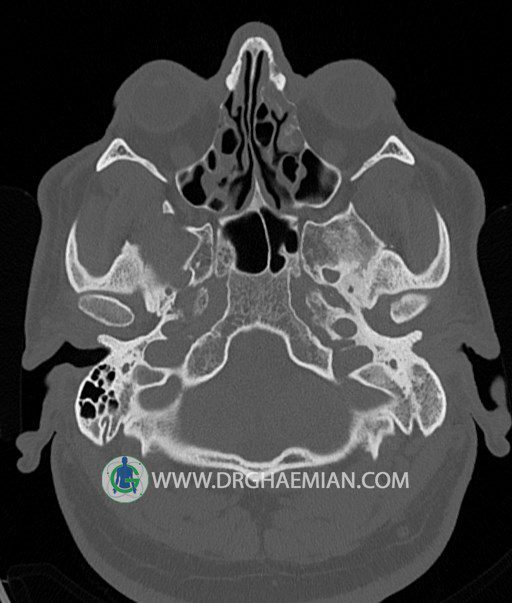

سی تی اسکن گوش داخلی به رادیولوژیست اجازه می دهد تا سطوح مختلف، یا اسلایس هایی از استخوان های که از جمجه به گوش می روند را از طریق امواج ایکس چرخشی مشاهده کند. در این کیس اودیت مدیا، ماستوئیدیت مزمن، اوتیت خارجی، انحراف سپتوم بینی، کونکا بولوزا و افزایش ضخامت سینوس ها مشاهده می شود.

در HRCT از استخوان تمپورال با مقاطع آگزيال ، ساژيتال و کرونال ظريف ( 0.6 mm ) :

– نماي کوکلهآي دو طرف با 2.5 دور گردش مجرا

– نماي cochlear aqueduct

– نماي semicircular canal خلفي ، لترال ، فوقاني و وستيبول

– استخوانچه هاي گوش داخلي شامل malleus ، incus و stapes (دنسيتي و رديف استخوانچه ها )

– نماي oval window و round window ، tympanic cavity ، attic و کانال گوش داخلي

– کانال عصب فاشيال و مسير ان از ناحيه کانال گوش داخلي ، geniculate ganglion تا محل خروج ان از stylomastoid foramen

– نماي tympanic membrane ، کانال ICA ، بولب جوگولار دو طرف

در حد طبيعي است .

– اپاسيتي گوش مياني چپ ناشي از وجود دانسيته نسج نرمي دراطراف استخوانچه ها همراه با اروژن اسکوتوم و

استخوانچه ها بدون جابجايي در رديف استخوانچه ها مشهود است که مطرح کننده اوتيت مديا همراه با نشانه

هاي مشکوک به کولستئاتوم مي باشد .

– اپاسيتي و اسکلروزيس ماستوئيد چپ نشانه ماستوئيديت مزمن

– اپاسيتي کانال گوش خارجي ناشي از دانسيتي نسج نرمي مطرح کننده external otitis

– انحراف سپتوم مياني بيني به راست

– کونکا بولوزا در کونکاي مياني چپ و

– افزايش ضخامت مخاطي در سينوس هاي اتموئيد و ماگزيلاري

اپاسيته